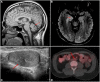

A 44-year-old man presented with cerebellar ataxia and limbic encephalitis and was ultimately diagnosed with metastatic germ cell neoplasm resulting from a "burned out" primary testicular tumor. The patient had progressive ataxia, leading to a thorough investigation for infectious, autoimmune, metabolic, and malignant causes of acquired cerebellar ataxia that revealed no significant findings. Testicular sonography demonstrated a possible right testicular lesion that was not confirmed on radical inguinal orchiectomy. F18-FDG positron emission tomography/computerized tomography scan revealed a solitary retroperitoneal lesion, concerning for metastatic disease but not amenable to percutaneous biopsy. A robotic retroperitoneal lymph node dissection was performed and pathology revealed a CD117-positive metastatic seminoma leading to appropriate germ cell tumor-directed chemotherapy. After completing chemotherapy and during 1 year of follow-up, there has been a gradual improvement of the patient's neurological manifestations.